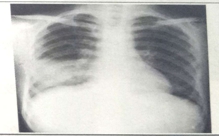

试题1:男性,26岁,受凉后寒颤高热,咳嗽,咳铁锈色痰5天(2分)

A.肺癌

B.气胸

C.正常胸片

D.肺炎

E.胸腔积液

答案:D